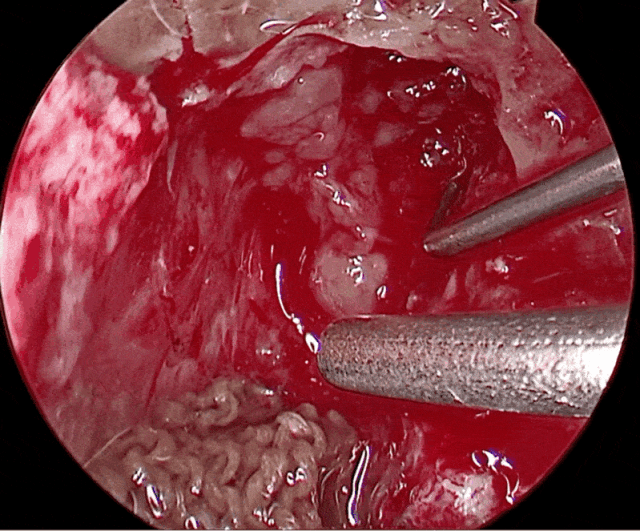

内镜视野

45度神经内镜下

将内听道底部肿瘤切除

内听道扩大明显,内听道底很深,术中内听道后壁磨除超过一公分,仍无法触及内听道底,后改为45度神经内镜下用带角度的刮匙将内听道底部肿瘤切除,在内镜下面神经在内听道壁左侧。